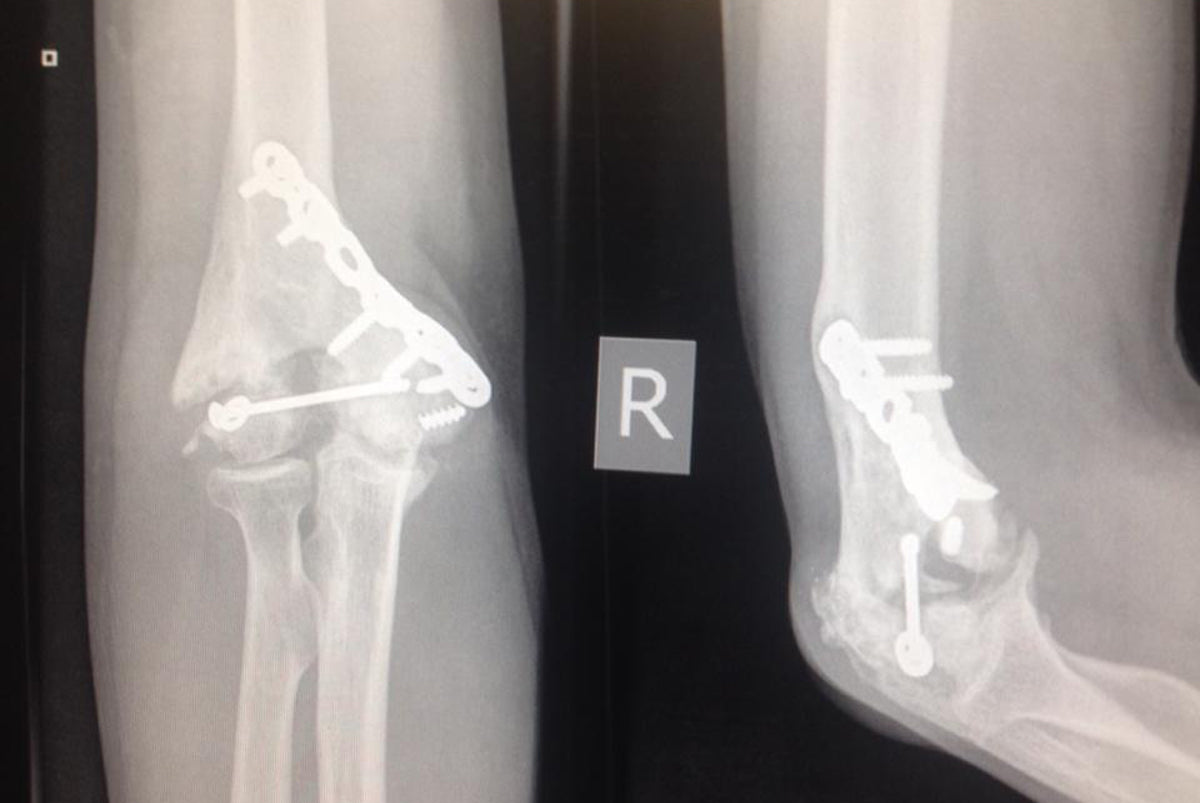

What I have is traumatic arthritis along the ankle joint, left over from the bone infection that led to the collapse of my lower leg and several limb reconstruction operations and two external fixators.

In order to stop the pain they need to stop the movement in the joint.

Best case scenario is they'll screw in two bolts through my tibia and talus. Remove the dead bone and replace it with bone from my fibia. After this the joint needs to be completely immobile for up to 12 weeks and a further 12 weeks of light movement and non full weight bearing.

That's the best case, however I have to be prepared to wake up with another external fixator and if there's not enough quality bone in the fibia they'll take a graft from my hip involving more pain and longer recovery.